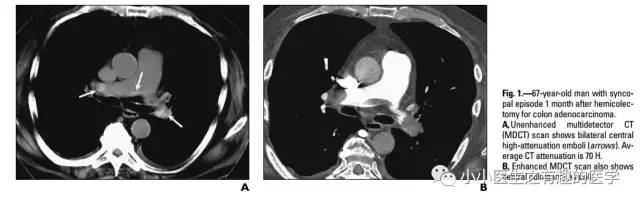

作者单位:Department of Radiology, Thoracic Imaging Section, San Francisco General Hospital。旧金山总医院。

如图,高密度影的那一条。不怕,有增强CT证实。

上面图片的英文原版: